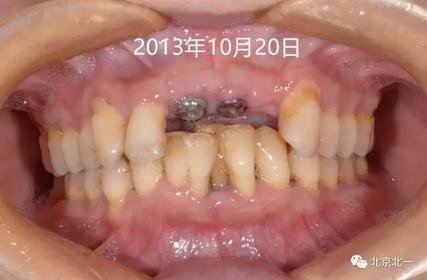

圖三:五月后二期手術(shù)

圖四:牙齦袖口,未做牙齦成形。

圖五:戴入基臺,采用粘接固位。